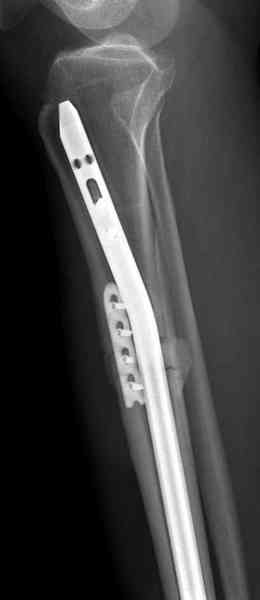

Оперирован в военном госпитале с заменой сегмента

аллокостью большеберцовой кости и после демобилизации явился для постоянного наблюдения по месту жительства.

Наши имели проблему со сращением, пришлось им сделать динамизацию, дополнительную аутопластику.

Снимки представлены.